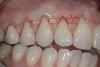

A patient presented with moderate recession requiring root coverage and increased thickness of the alveolar housing (Figure 9). A series of parallel incisions was completed using instruments made specifically for microsurgery; these incisions were performed utilizing high magnification (ie, 5.5 magnification via loupes). The distance between the incisions was roughly the amount of root coverage necessary on the adjacent teeth (Figure 10).25

The CTG was then harvested from the palate as previously described and placed over the roots (Figure 11). The primary flap was advanced to cover the graft; a dual blood supply was assured from the underlying tissue and the overlying flap. Atraumatic suturing was performed using fine sutures (eg, Resorba® 6-0/7-0 Resolon™, Osteogenics Biomedical, osteogenics.com) to approximate the flap margins.

After 1 week, rapid healing and good closure were observed. After 2 years, complete root coverage was visible, a thicker alveolar housing was achieved, and the gingiva was more resistant to future breakdown (Figure 12).

Fig 9. Preoperative view of a patient with moderate recession requiring root coverage and increased thickness of the alveolar housing.

Fig 12. After 2 years, note complete root coverage, thicker alveolar housing, and strengthened gingiva.